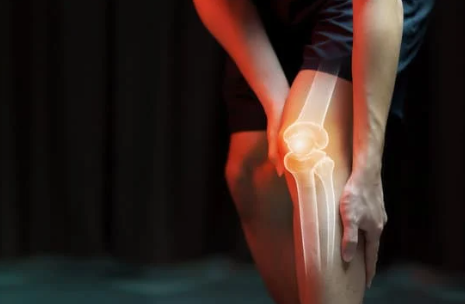

무릎 관절 통증은 많은 사람들이 경험하는 흔한 문제로, 일상생활에서 큰 불편함을 초래할 수 있습니다. 특히 활동적인 사람이나 중장년층은 이러한 증상으로 인해 운동이나 일상적인 활동이 제한될 수 있습니다. 무릎 통증이 발생했을 때, 대부분의 사람들은 어떻게 대처해야 할지 막막하게 느끼곤 합니다. 본 글에서는 무릎 관절 통증의 원인, 증상, 그리고 효과적인 치료와 예방 방법을 소개하여 여러분의 고민을 해결하는 데 도움을 드리겠습니다.

무릎 관절 통증의 원인은 다양합니다. 다음은 대표적인 원인들입니다.

- 퇴행성 관절염: 나이가 들면서 무릎 관절의 연골이 마모되어 발생하는 질환입니다. 통증과 함께 부종이 동반될 수 있으며, 움직임이 제한됩니다.

- 외상: 스포츠 활동이나 사고로 인한 외상은 무릎의 인대나 연골에 손상을 줄 수 있습니다. 이로 인해 급작스러운 통증 및 부기가 발생할 수 있습니다.

- 염증성 질환: 류마티스 관절염과 같은 염증성 질환은 면역 시스템에 문제가 생겨 무릎 관절의 염증과 통증을 유발합니다.

- 과사용: 무리한 운동이나 반복적인 동작은 무릎 관절에 과도한 스트레스를 주어 통증을 유발할 수 있습니다. 특히, 달리기나 점프가 많은 운동을 하는 경우 위험이 증가합니다.